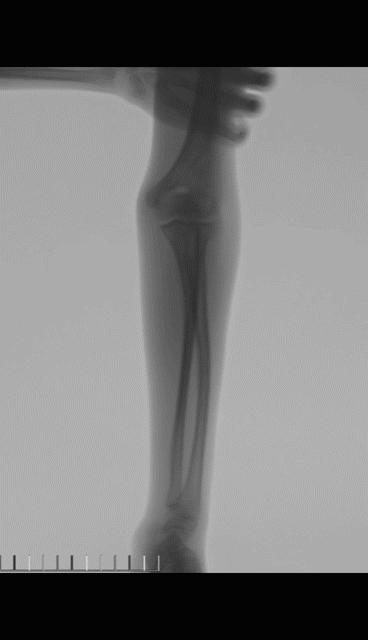

老师: 下面两个病例,分别是9岁4个月男孩的前臂中段骨折,保守治疗后3个月骨折对位、愈合良好。另外一个12岁男孩,早期外院保守治疗,三周时骨折再移位,于我院再次整复后恢复满意。